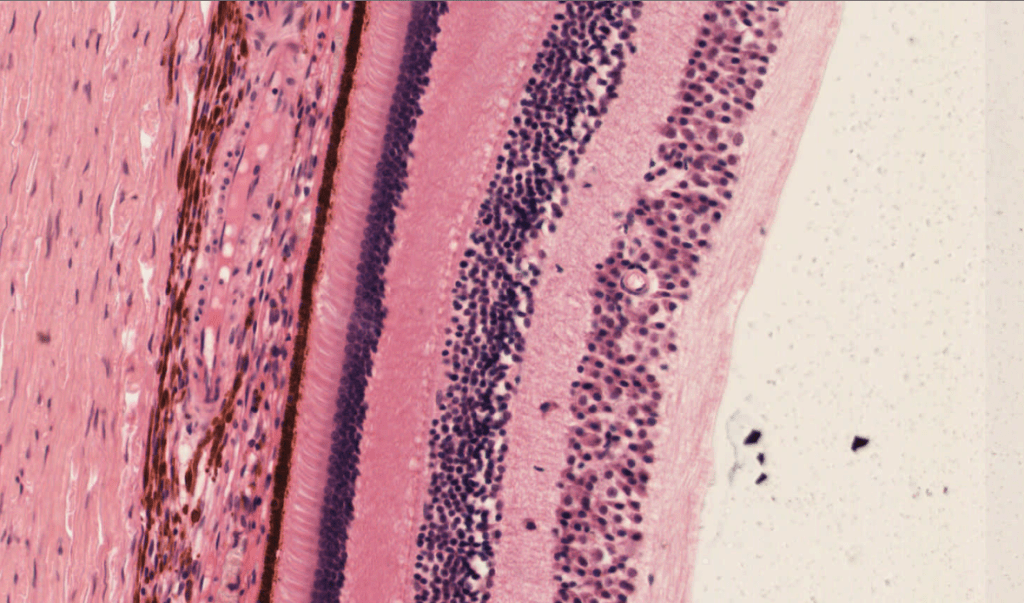

RETINA

- Epitelio pigmentario: Es la capa más externa de la retina.

- Capa de fotorreceptores: Está formada por los segmentos externos de los fotorreceptores.

- Limitante externa: No es una membrana, sino uniones tipo zónula adherens entre los fotorreceptores y las cél. de Müller.

- Nuclear o granular externa: Formada por los núcleos celulares de los fotorreceptores.

- Plexiforme externa: Sinapsis entre fotorreceptores y las cél. bipolares.

- Nuclear o granular interna: Encontramos núcleos celulares de las cél. bipolares, las cél. horizontales y las cél. amacrinas

- Plexiforme interna: Sinapsis entre células bipolares, amacrinas y ganglionares.

- Células ganglionares: Núcleos de las células ganglionares.

- Fibras nerviosas: Axones de cél. ganglionares.

- Limitante interna: Separa la retina del humor vítreo.